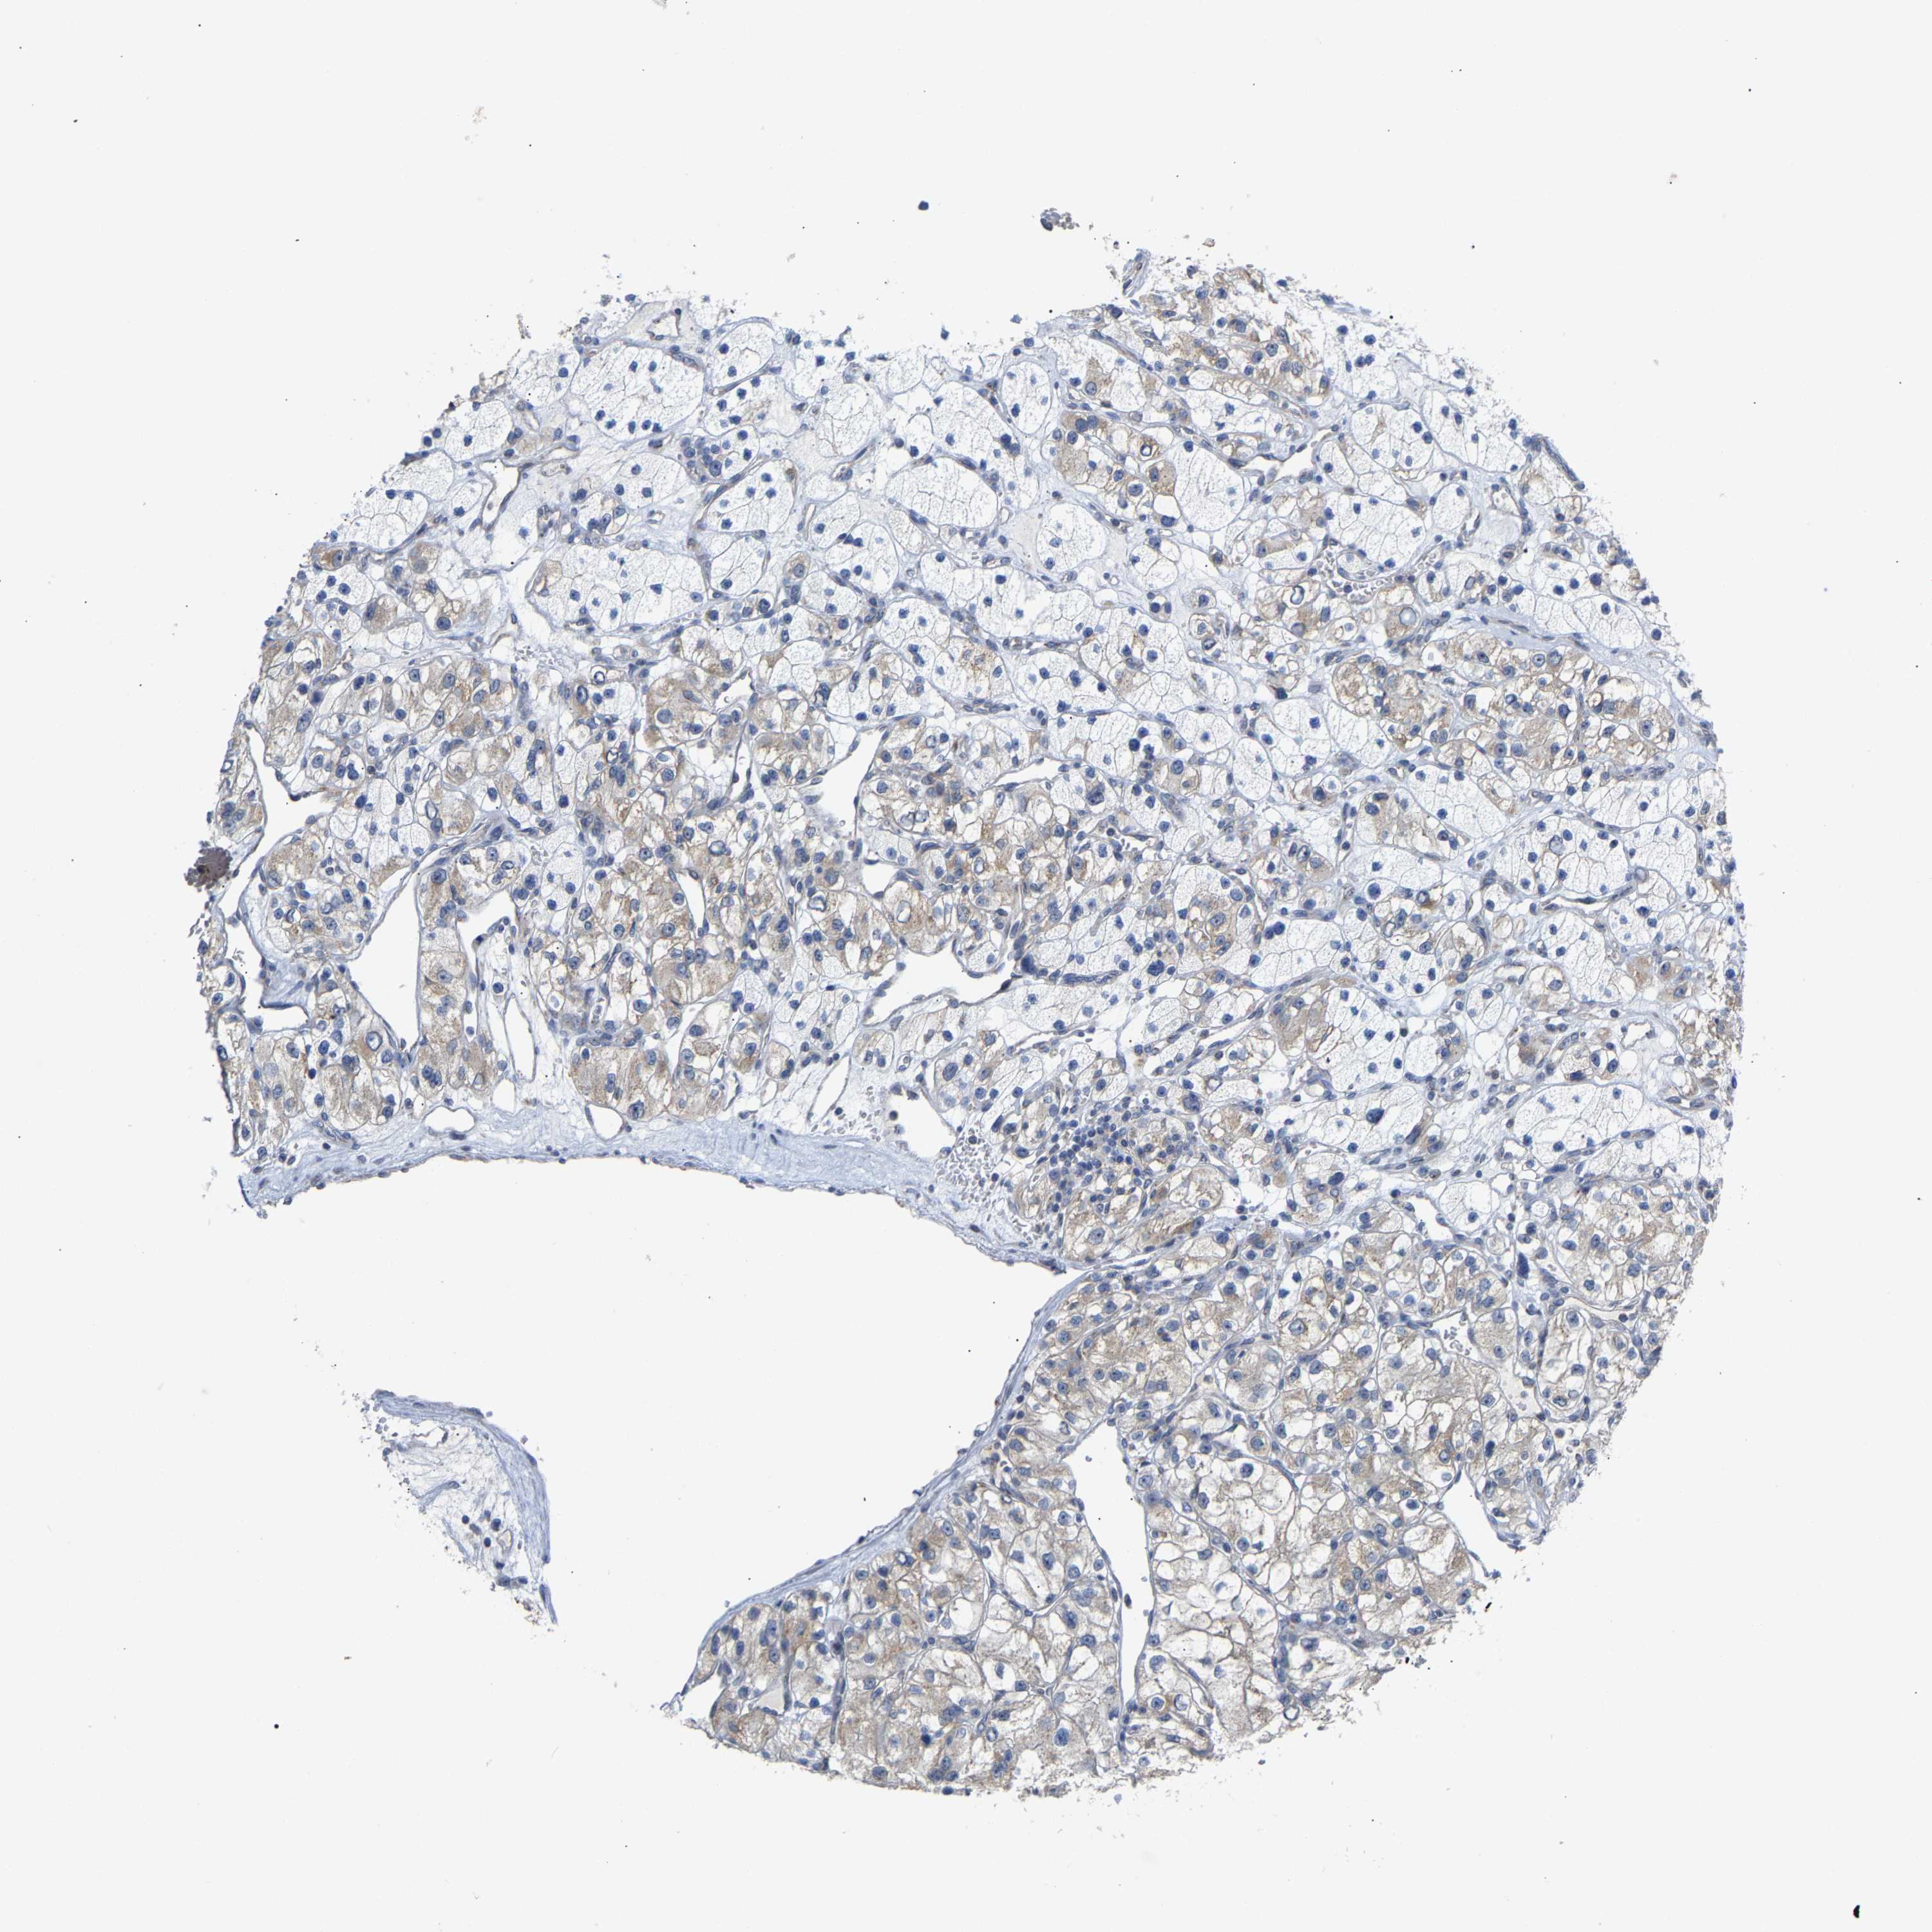

KIDNEY RENAL PAPILLARY CELL CARCINOMA (TCGA) - Interactive survival scatter ploti

The Survival Scatter plot shows the clinical status (i.e. dead or alive) for all individuals in the patient cohort, based on the same data that underlies the corresponding Kaplan-Meier plots. Patients that are alive at last time for follow-up are shown in blue and patients who have died during the study are shown in red.

The x-axis shows the expression levels (FPKM) of the investigated gene in the tumor tissue at the time of diagnosis. The y-axis shows the follow-up time after diagnosis (years). Both axes are complimented with kernel density curves demonstrating the data density over the axes. The top density plot shows the expression levels (FPKM) distribution among dead (red) and alive patients (blue). The right density plot shows the data density of the survived years of dead patients with high and low expression levels respectively, stratified using the cutoff indicated by the vertical dashed line through the Survival Scatter plot. This cutoff is automatically defined based on the FPKM cutoff that minimizes the p-score. The cutoff can be changed by dragging the vertical line or by entering a cutoff value in the square labeled "Current cut-off".

Under the Survival Scatter plot the p-score landscape (black curve; left axis) is shown together with dead median separation (red curve; right axis). Dead median separation is the difference in median mRNA expression between patients who have died with high and low expression, respectively. It is calculated as follows: median FPKM expression of dead patients with high expression - median FPKM expression of dead patients with low expression. This is intended to aid the user in visually exploring custom cutoffs and the associated p-scores and dead median separation.

Individual patient data is displayed and can be filtered by clicking on one or more of the category buttons on the top of the page. Categories describing expression level and patient information include: high, low, alive, dead, female, male and tumor stages. The scale of the x-axis can be toggled between linear and log-scale by clicking on the "x log" button. Mouse-over function shows TCGA ID, patient information and mRNA expression (FPKM) for each patient.

& Survival analysisi

Kaplan-Meier plots summarize results from analysis of correlation between mRNA expression level and patient survival. Patients were divided based on level of expression into one of the two groups "low" (under cut off) or "high" (over cut off). X-axis shows time for survival (years) and y-axis shows the probability of survival, where 1.0 corresponds to 100 percent.

PCNT is not prognostic in Kidney Renal Papillary Cell Carcinoma (TCGA)

Best expression cut offi

Based on the FPKM value of each gene, patients were classified into two groups and association between prognosis (survival) and gene expression (FPKM) was examined. The best expression cut-off refers the FPKM value that yields maximal difference with regard to survival between the two groups at the lowest log-rank P-value. Best expression cut-off was selected based on survival analysis .

When clicking on this number, the vertical dashed line indicating cut-off, the interactive survival plot, and the Kaplan-Meier curve will be adjusted to show results based on the best expression cut-off.

: 5.44